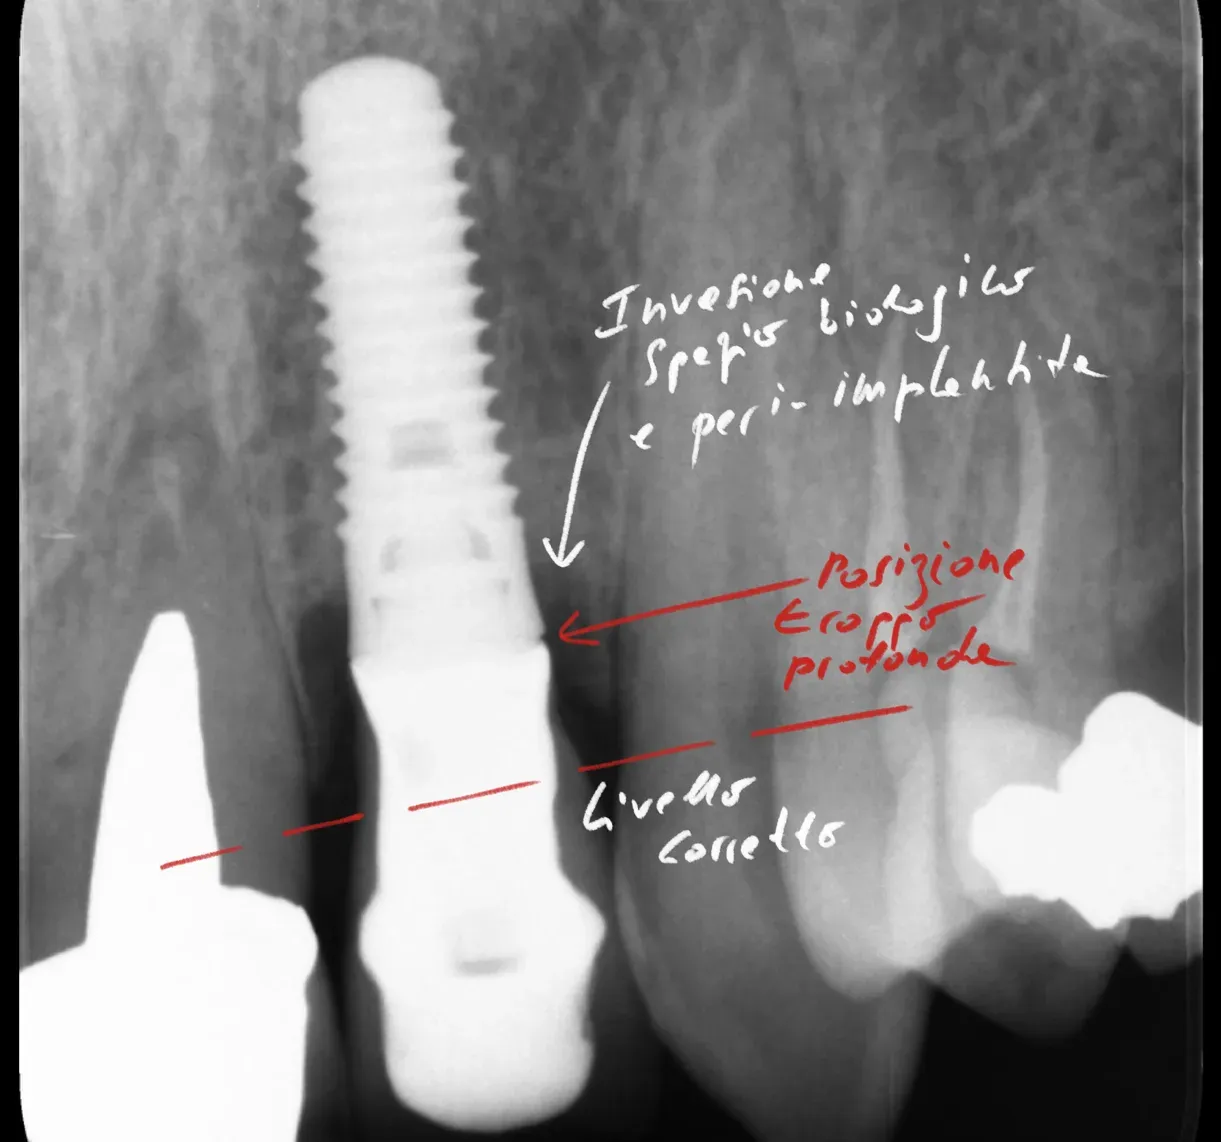

Radiografia di un impianto affetto da peri-implantite da posizionamento errato